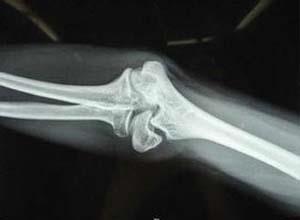

简介肱骨上端有三个骨骺,即肱骨头,大结节及小结节,顺序于1岁、3岁及5岁出现骨骺,于5~8岁三个骨骺融合成为肱骨上端一个骨骺,至19~21岁骨骺与肱骨干融合。因此,肱骨上端骨骺分离多见于7~18岁;以后成人可发生肱骨解剖颈骨折。由于肱骨上端在额状面上,肱骨干骺端形成15°左右的后倾角,骨骺中心位于骺板的内后侧,因此,沿肱骨干向上传导的暴力作用于骺板,产生剪切应力,造成骨折线呈斜形,前外侧部分经过骺板面骨骺分离,后内侧部分经过干骺端时,形成一个三角形骨片,骨折线倾斜程度随年龄而异,年龄越大则骨折线经过骺板之横行距离越短,干骺端骨折片越大,且使倾斜面距离越长,骨折端越不稳定。